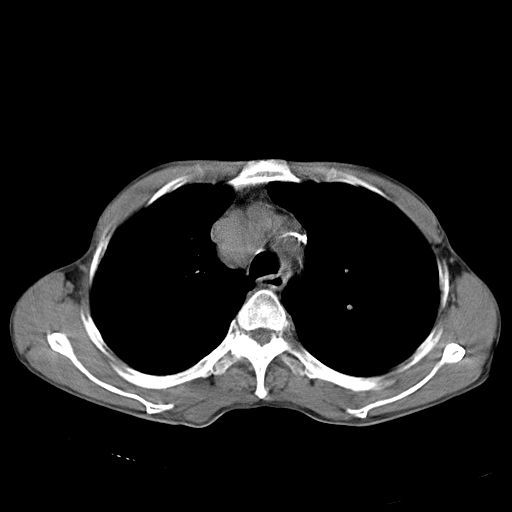

以下是引用苯小孩在2007-5-24 12:47:00的发言:[br]右侧肺门处不均匀密度软组织块影,远端肺组织见斑片模糊影,纵隔内淋巴结明显肿大,边界不清.<纵隔窗第12层面支气管内似见软组织结节>[br]考虑:1、右侧中央性肺癌并阻塞性肺炎并纵隔淋巴结转移可能性大.建议强化或纤支镜进一步检查.[br]2、隆突下淋巴结肿大/食道病变?请做鉴别检查.

以下是引用zhangzhongshou在2007-5-24 12:55:00的发言:[br]1、右肺中叶中心型肺癌并右肺门、隆突下、纵隔淋巴结转移。右肺中叶阻塞性肺炎。

以下是引用jw-830在2007-5-24 15:24:00的发言:[br][br] [br] 考虑右肺中央型肺癌并阻塞性炎症,右肺门及纵隔淋巴结转移。 [br] [br][br]